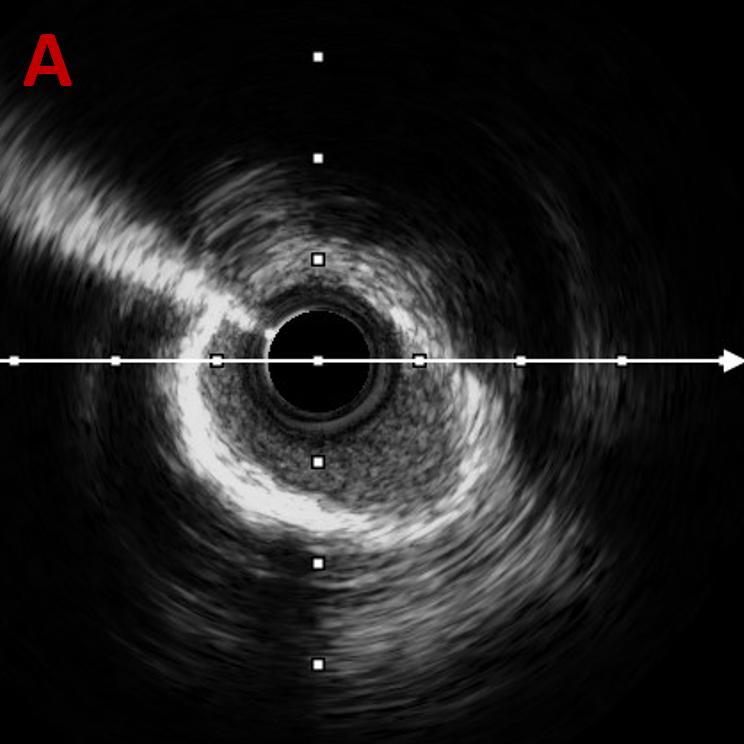

复查IVUS可见:LAD多处环形钙化,原支架贴壁不良,支架远端导丝走形在支架外,IVUS指导下重新调整导丝进入支架

经后扩复查IVUS

-

LAD中远段支架贴壁良好,LAD开口显示有明显支架贴壁不良

LAD近端EEM直径4.74mm,送入4.5*15 NC进行后扩